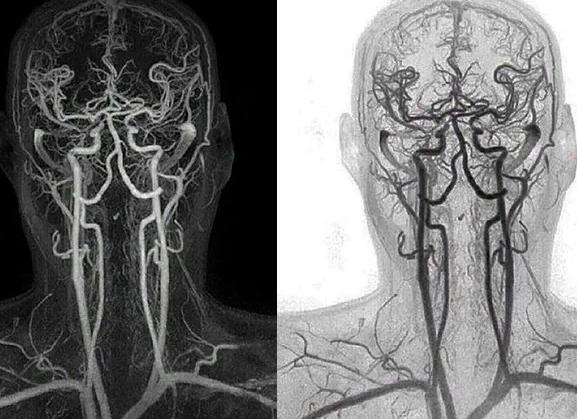

Что показывает КТ сосудов головного мозга и чем отличается от МРТ?

С помощью компьютерной томографии можно исследовать различные структуры человеческого организма. Такая диагностика привлекает информативностью. Одно из направлений сканирования – КТ сосудов головного мозга или ангиография.

Что показывает КТ сосудов мозга?

Компьютерная томография позволяет исследовать сосуды головного мозга до 1 мм в диаметре, причем в разных проекциях и плоскостях.

Отличия КТ сосудов от МРТ

Основное отличие КТ от МРТ сосудов головного мозга заключается в принципе работы этих методов. Компьютерная томография основана на рентгеновском излучении, потому больше информативна в отношении костных структур, что важно при их нарушении и черепно-мозговых травмах. Магнитно-резонансная томография работает за счет магнитных полей и радиочастотного излучения, потому лучше визуализирует мягкие ткани и сосуды.